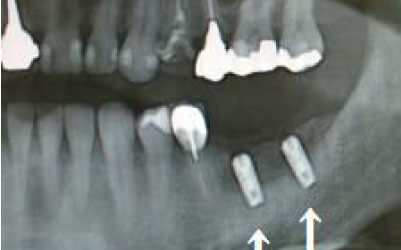

また、インプラント治療の前に骨を増やす治療が必要な場合は、さらに約3ヶ月ほど追加でかかることがあります。

CTでは、骨や歯の状態を3Dで確認でき、正確な距離の測定も行えます。

骨の厚さや傾き、神経の位置などを事前にしっかりと測定することで、安全にインプラントを行うことができます。

骨が薄い場合、そのままインプラントを行うのはお勧めできません。

ただし、事前に骨を増やす治療を行ったり、インプラントと同時に骨を増やす治療を行えば、インプラントは可能です。

ただし、事前にCTで三次元的に神経との距離を測り、治療計画を慎重に立てれば、心配することはありません。

また、当院では過剰に削らないようにするためのストッパーも使用しています。